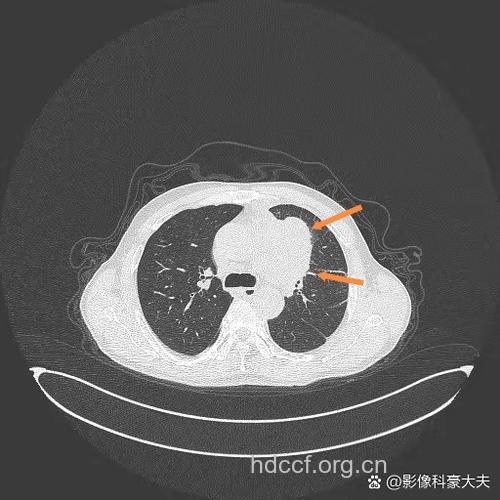

(3)肺结核患者经治疗病情稳定后,突然病灶又复发恶化,肺的某段或叶有炎症浸润,局部肺气肿或肺不张者,都应高度警惕并做进一步检查。